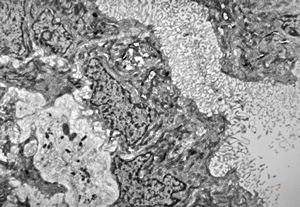

F,31y. | demyelinating hypertrophic neuropathy - n. suralis- bands of Büngner with collagen-filled pockets